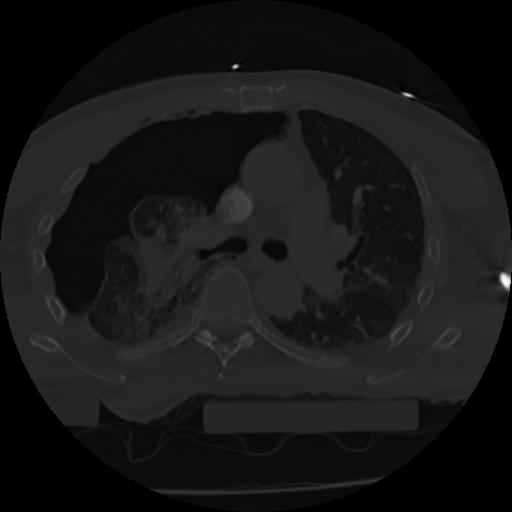

22 ANGIO,CE,Vol,0.5,ANGIO,,